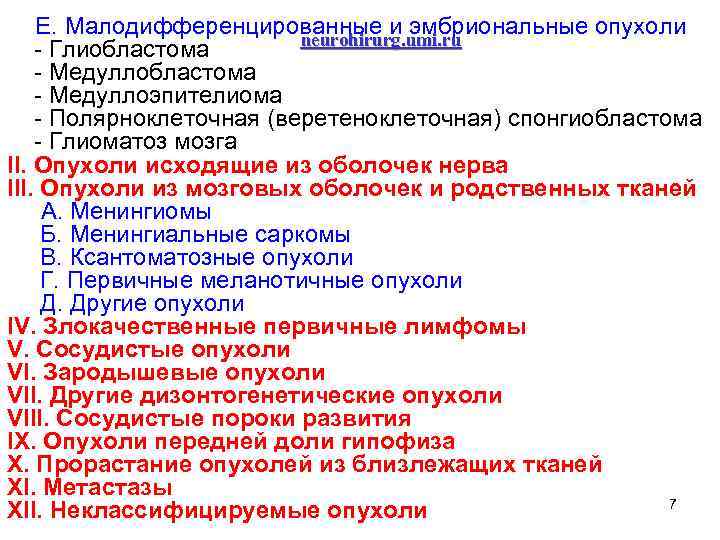

Е. Малодифференцированные и эмбриональные опухоли neurohirurg. umi. ru - Глиобластома - Медуллобластома - Медуллоэпителиома - Полярноклеточная (веретеноклеточная) спонгиобластома - Глиоматоз мозга II. Опухоли исходящие из оболочек нерва III. Опухоли из мозговых оболочек и родственных тканей А. Менингиомы Б. Менингиальные саркомы В. Ксантоматозные опухоли Г. Первичные меланотичные опухоли Д. Другие опухоли IV. Злокачественные первичные лимфомы V. Сосудистые опухоли VI. Зародышевые опухоли VII. Другие дизонтогенетические опухоли VIII. Сосудистые пороки развития IX. Опухоли передней доли гипофиза X. Прорастание опухолей из близлежащих тканей XI. Метастазы 7 XII. Неклассифицируемые опухоли